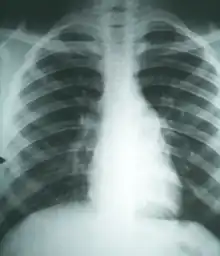

Examen directo de muestras de lesiones Cultivo Biopsia Pruebas inmunológicas Radiografías y tomografía computarizada | |

- Clínico-epidemiológico: bastante característico, teniendo en cuenta la procedencia o estancia en zonas enzoóticas y el cuadro respiratorio progresivo.

- Lesional: patognomónico a escala microscópica, no es tan característico el macroscópico, que se puede confundir con blastomicosis e histoplasmosis. Histológicamente las lesiones más comunes (34 %) son los granulomas supurativos, sin excluir la presencia de infiltrado linfoplasmocitario, granuloma sarcoidal, inflamación linfoplastrofílica, granuloma necrotizante e inflamación eosinofílica.[1]